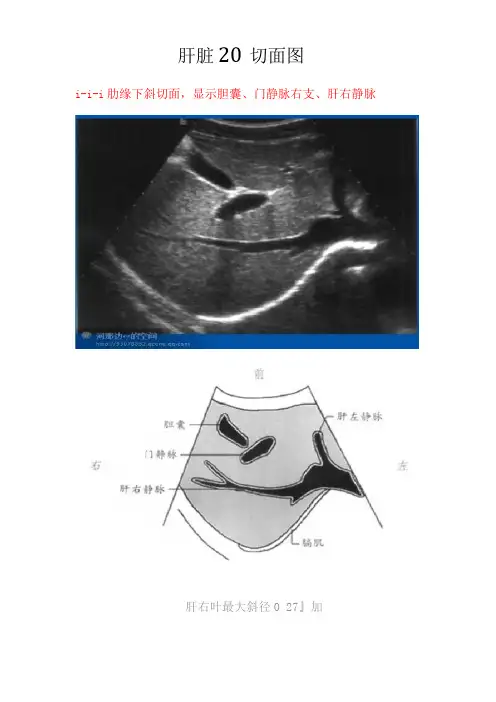

肝脏20切面图1-1-1肋缘下斜切面,显示胆囊、门静脉右支、肝右静脉11-I-2肋缘下斜切面,显示下腔静脉、肝左静脉、肝中静脉、肝右静脉21-1-3剑下肝左叶斜切面,显示肝圆韧带、腹主动脉、下腔静脉、门静脉31-1-4剑下肝左叶斜切面,显示肝左叶、肝尾状叶、静脉韧带、腹主动脉、下腔静脉41-1-5右第五肋间斜切面,显示门静脉、肝左静脉外下段、门静脉左支外上段、肝左静脉51-1-6右第六或第七肋间斜切面,显示右肝管、肝总管及胆总管、肝动脉、门静脉、下腔静脉6管、右肝管、下腔静脉、肝右静脉7左肝管、右肝管、下腔静脉、肝圆韧带81-1-9经下腔静脉肝左叶矢状切面,显示下腔静脉、门静脉矢状部、肝左静脉、左叶间静脉、肠系膜上静脉91-1-10经腹主动脉肝左叶矢状切面,显示腹主动脉、肝左静脉、门静脉、脾动脉、脾静脉、腹腔动脉101-1-11剑下肝左叶斜切面静脉左支矢状部、显示胆囊、肝圆韧带、门静脉左支横部、左外叶下段支、左外叶上段支、静脉韧带、下腔静脉111-1-12肝左叶矢状切面,显示下腔静脉、门静脉、肝左静脉、静脉韧带121-1-13肝右叶矢状切面,显示下腔静脉、肝中静脉、门静脉右支、右肾静脉、右肾动脉131-1-14肝右叶纵切面,显示与右肾的界面141-1-15肝右叶纵切面,显示隔顶部与胸腔15161-1-16肝左叶横切面,显示静脉韧带、腹主动脉、下腔静脉、尾状叶171-1-17肝左叶横切面,显示肝圆韧带181-1-18右肝横切面,显示门静脉左右支191-1-19肋缘下右肝横切面,显示右肝下缘201一1-20肝右叶横切面,显示隔顶部与胸腔2122。

肝脏20切面图1-1-1肋缘下斜切面,显示胆囊、门静脉右支、肝右静脉1-I-2肋缘下斜切面,显示下腔静脉、肝左静脉、肝中静脉、肝右静脉1-1-3剑下肝左叶斜切面,显示肝圆韧带、腹主动脉、下腔静脉、门静脉1-1-4剑下肝左叶斜切面,显示肝左叶、肝尾状叶、静脉韧带、腹主动脉、下腔静脉1-1-5右第五肋间斜切面,显示门静脉、肝左静脉外下段、门静脉左支外上段、肝左静脉1-1-6右第六或第七肋间斜切面,显示右肝管、肝总管及胆总管、肝动脉、门静脉、下腔静脉1-1-7经第一肝门右肋下斜切面,显示胆囊、门静脉、左肝管、右肝管、下腔静脉、肝右静脉1-1-8经第一肝门右肋下斜切面,显示腹主动脉、门静脉、左肝管、右肝管、下腔静脉、肝圆韧带1-1-9经下腔静脉肝左叶矢状切面,显示下腔静脉、门静脉矢状部、肝左静脉、左叶间静脉、肠系膜上静脉1-1-10经腹主动脉肝左叶矢状切面,显示腹主动脉、肝左静脉、门静脉、脾动脉、脾静脉、腹腔动脉1-1-11剑下肝左叶斜切面静脉左支矢状部、显示胆囊、肝圆韧带、门静脉左支横部、左外叶下段支、左外叶上段支、静脉韧带、下腔静脉1-1-12肝左叶矢状切面,显示下腔静脉、门静脉、肝左静脉、静脉韧带1-1-13肝右叶矢状切面,显示下腔静脉、肝中静脉、门静脉右支、右肾静脉、右肾动脉1-1-14肝右叶纵切面,显示与右肾的界面1-1-15肝右叶纵切面,显示隔顶部与胸腔1-1-16肝左叶横切面,显示静脉韧带、腹主动脉、下腔静脉、尾状叶1-1-17肝左叶横切面,显示肝圆韧带1-1-18右肝横切面,显示门静脉左右支1-1-19肋缘下右肝横切面,显示右肝下缘1一1-20肝右叶横切面,显示隔顶部与胸腔THANKS !!!致力为企业和个人提供合同协议,策划案计划书,学习课件等等打造全网一站式需求欢迎您的下载,资料仅供参考!。

肝脏20切面图

i-i-i肋缘下斜切面,显示胆囊、门静脉右支、肝右静脉

肝右叶最大斜径0 27』加